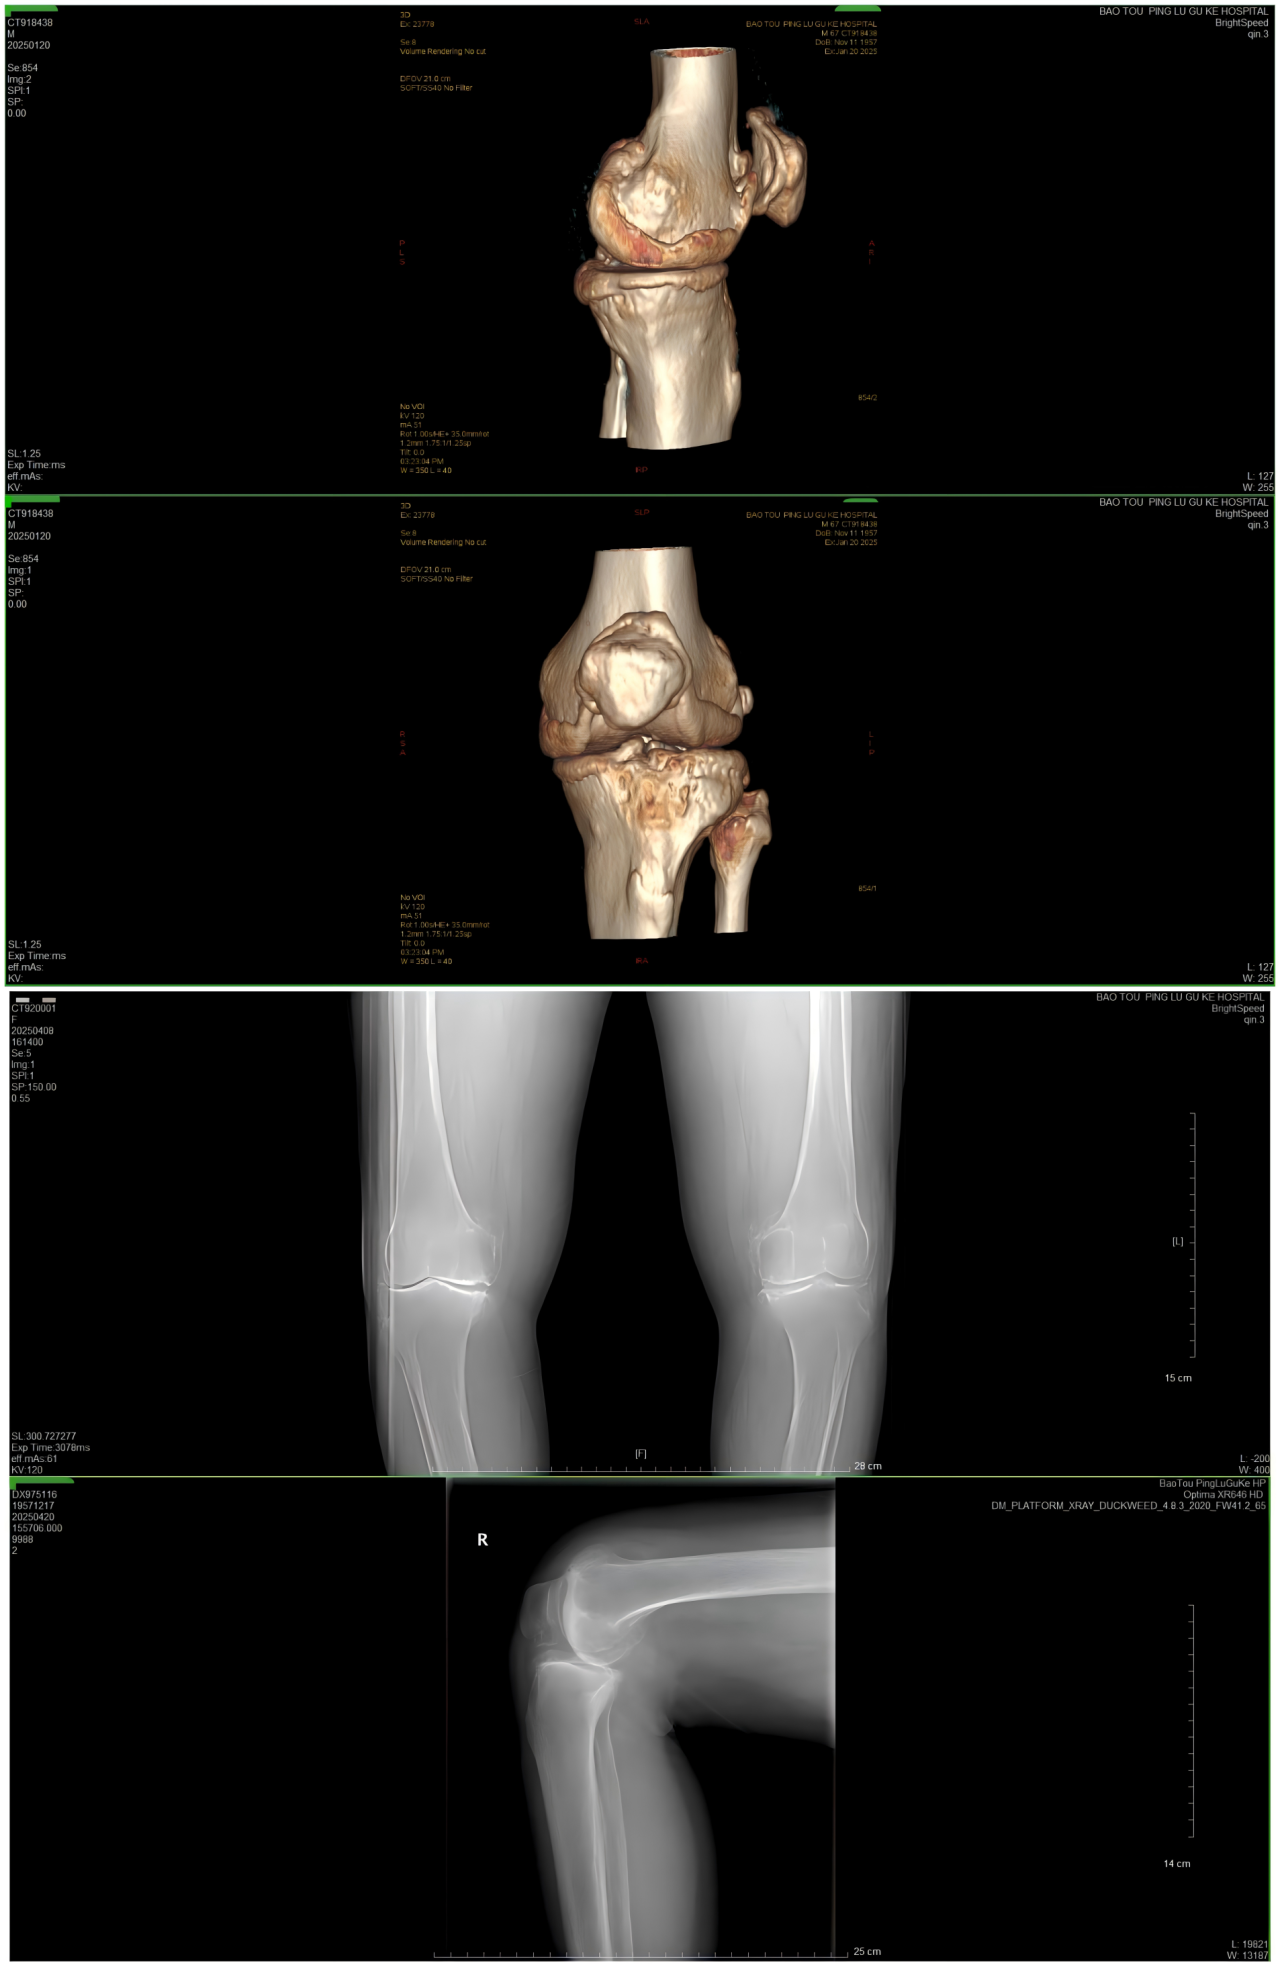

患者术后X光扫描

患者术前VS术后对比

①站立位X光片中显示关节间隙消失或极度狭窄